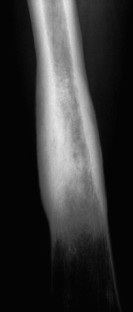

The SAPHO syndrome was a term coined to include a variety of musculoskeletal disorders associated with skin conditions, mainly palmoplantar pustulosis and acne conglobata. It is more correctly a spectrum which includes the following: skin lesions, osteoarticular manifestations of synovitis hyperostosis and osteitis affecting particular target sites, and·a clinical course marked by relapses and remissions. The major sites of involvement are the anterior chest wall, the spine, long bones, flat bones, and large and small joints. The distribution and severity of involvement varies from the adult to the pediatric form of chronic recurrent multifocal osteomyelitis (CRMO). The diagnosis of SAPHO syndrome is not difficult when the typical osteoarticular lesions are located in characteristic target sites. The diagnosis is more difficult if atypical sites are involved and there is no skin disease.